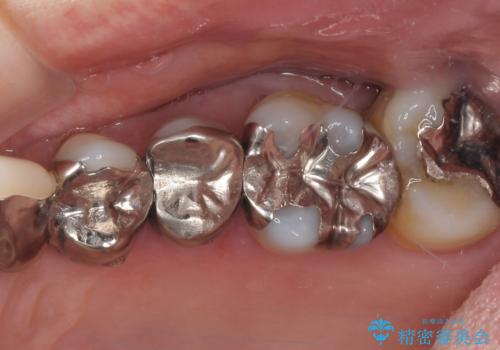

銀歯や入れ歯で汚い歯をきれいにしたい 総合歯科治療

歯並びや奥歯の痛み 色々と治したい 総合歯科診療

[MTMを行い歯の神経を保存] 歯周補綴ブリッジ